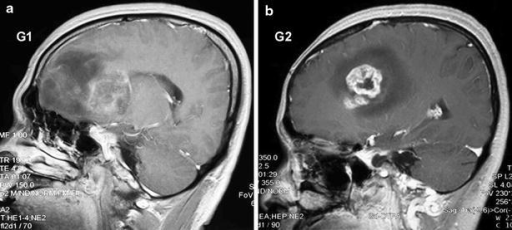

Puzzle 17

What's the Diagnosis?